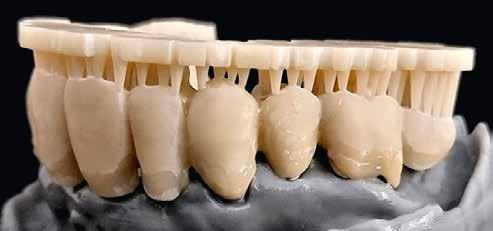

1–2. képek: Kiindulási helyzet.

3. kép: Új teleszkópos fogpótlás az 16, 15, 13, 23 és 27 fogakra.

Teleszkópos munka, élő eset bemutatásával ismertetem, mi az, ami már lehetséges. A munkaasztal-szkenneren kívül bevetésre került a digitális munkafolyamatok során egy intraorális szkenner (IOS) is. A 3D nyomtatású testek gyártása a laboratóriumban LCD- és DLP nyomtatókkal történt. A fémes komponenseket szelektív lézerolvasztásos (SLM) technológiával készíttettük.

Kiindulási helyzet

A páciens látlelete a következő:

• krónikus általános parodontitis

• a 24-től terjedő parodontális fekély

• hatástalan kapcsos felső fogpótlás (1-2. képek)

Terápia

A kezelőorvos (dr. Werner Knapp, Würzburg) ennek alapján a következő terápiát javasolta:

• a 24-es fog extrakciója, illetve az 12 és 22 fogak extrakciója előrehaladott szövetveszteség okán

• szisztematikus parodontitis-terápia

• új, teleszkóp-elhorgonyzású felső fogpótlás az 16, 15, 13, 23 és 27 fogak felhasználásával (3. kép)